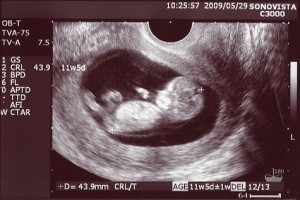

Саме зараз проводиться перше офіційне ультразвукове обстеження. Плід підріс вже настільки (БПР (відстань між тім'яними кістками) 18 мм, довжина стегна 7 мм, окружність грудей 20 мм, вага 11 грам, КТР складає 6.8 см.), його відмінно видно при ультразвуковому дослідженні і можна оцінити правильність його розвитку. Хоча стать ще не зможуть сказати, але зараз більш важливе здоров'я мами та її майбутнього малюка.